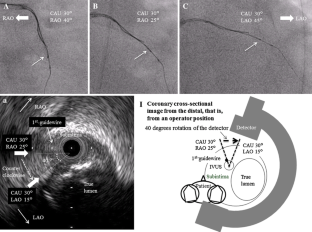

We describe an initial clinical chronic total occlusion (CTO) case in which CTO-specific intravascular ultrasound (IVUS): Navifocus WR was useful for navigating the second guidewire into the true lumen under the IVUS observation from the subintimal space.

Fig. 1